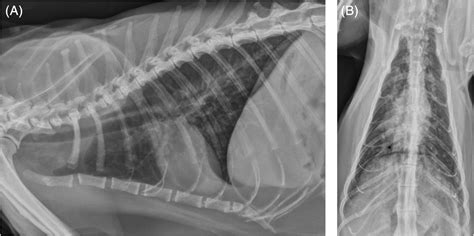

• Radiographs (X-rays): Chest X-rays can reveal inflammation, fluid, or other abnormalities in the lungs.